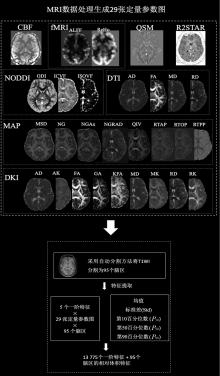

ZHANG R, WANG Y, WANG H, et al. Identification of neural alterations in patients with Crohn's disease with a novel multiparametric brain MRI-based radiomics model[J]. Insights Imaging, 2024,15(1):289. doi:10.1186/s13244-024-01859-6